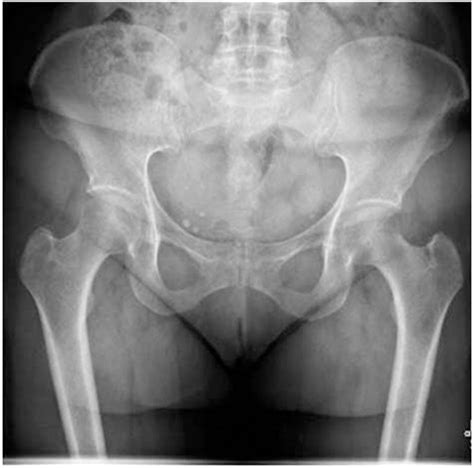

Diagnosing an SIF requires a high index of suspicion from healthcare providers, as standard X-rays often miss these fractures, especially in the early stages. More advanced imaging is typically necessary to confirm the diagnosis.

Imaging Modality Effectiveness for SIF

X-Ray Low sensitivity; often shows normal results even when a fracture exists.

MRI Gold standard; highly sensitive in detecting bone marrow edema and fracture lines.

CT Scan Good for visualizing the fracture line, but less sensitive than MRI for early stages.

Bone Scan Sensitive, but provides less anatomical detail than MRI or CT.